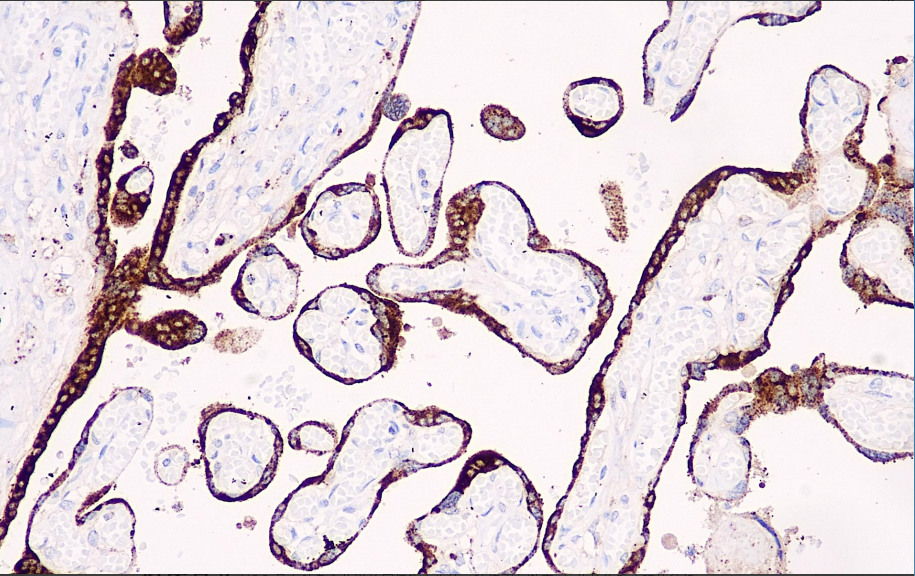

阳性对照: 胎盘

此抗体可以识别人绒毛膜促性腺激素(HCG),与促黄体生成素(LH)有轻微的交叉反应,胎盘和胎盘滋养层细胞为阳性表达,主要用于标记绒癌及检测分泌异位激素的肿瘤。

HCG抗体试剂可与HCG分子抗原特异性结合,含HCG抗体试剂的免疫组化试剂盒适用于绒癌及分泌异位激素的肿瘤的精准诊断。